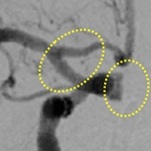

脳動脈瘤コイル塞栓術(血管内治療)

治療前(血管造影画像)

治療後(血管造影画像